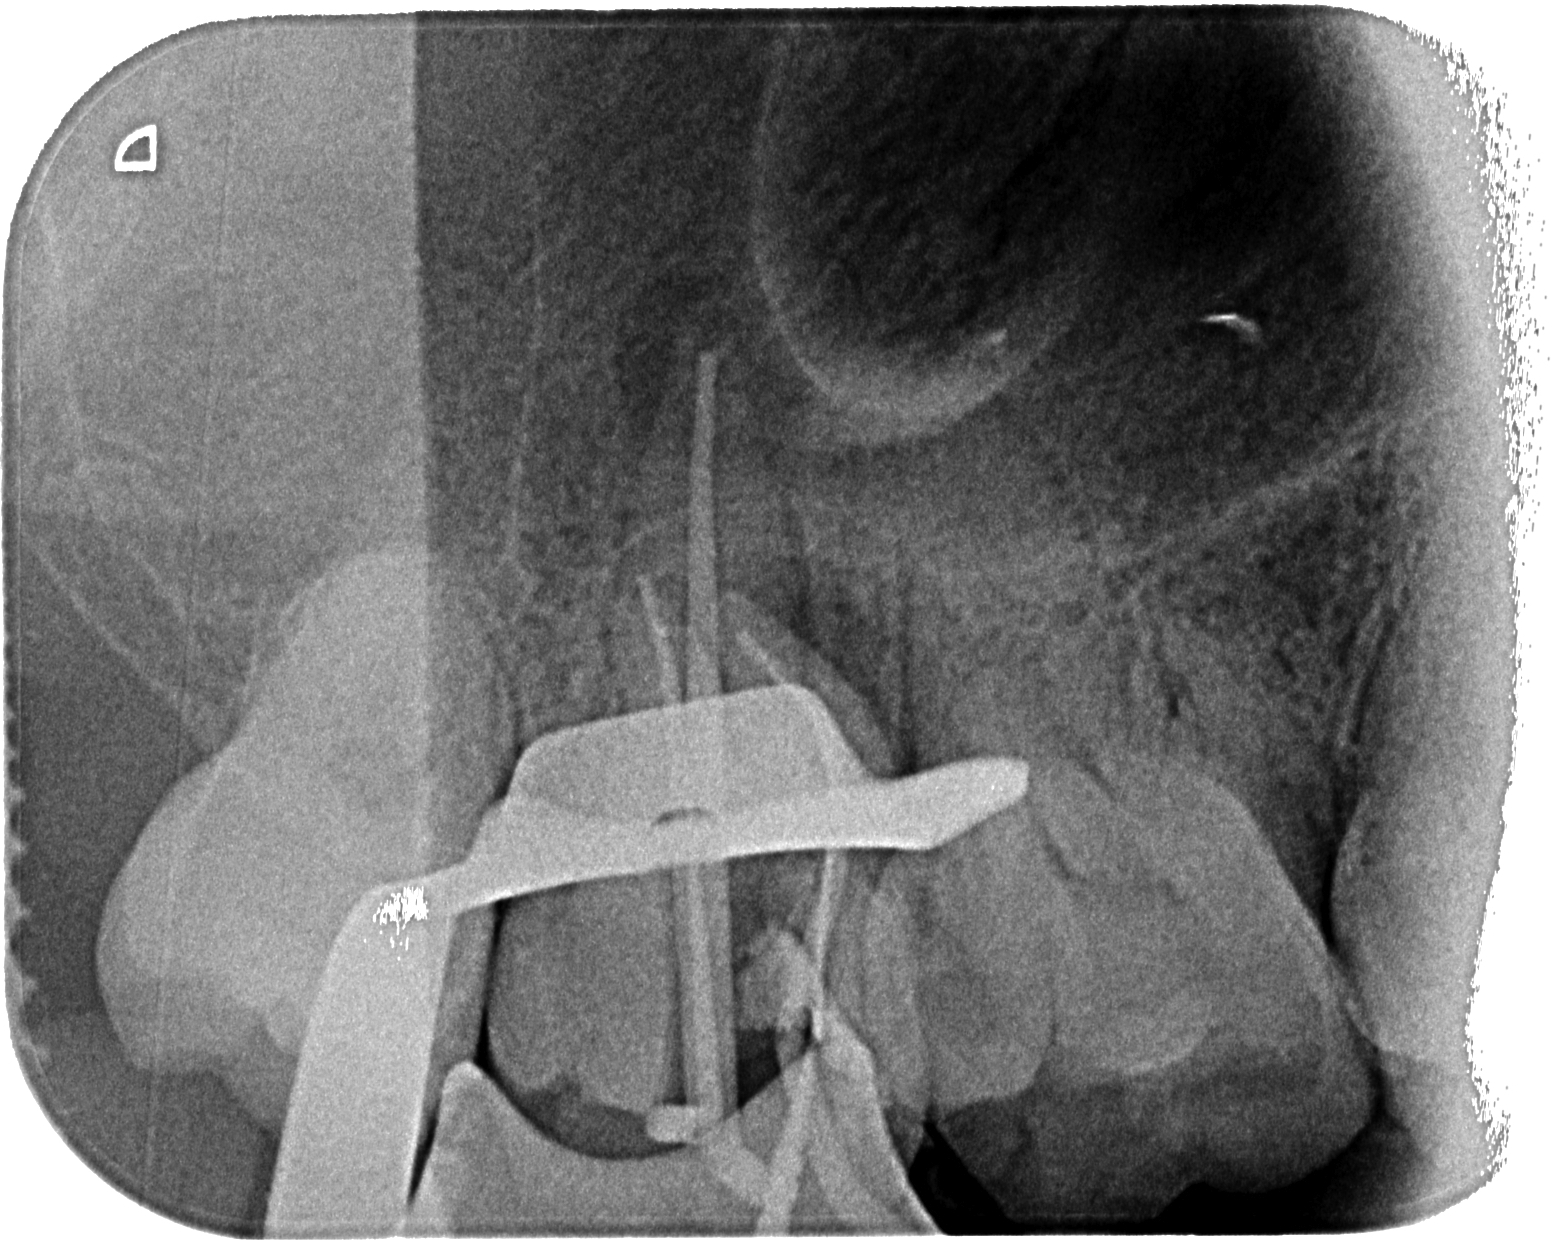

Stop Apical Endodoncia . This retrospective study evaluated cases of unintentional overfillings during root canal treatment for the fate of the extruded sealer and its influence on the outcome. Root canal shaping in the age of minimally invasive endodontics (mie) technology. The extent of the apical obturation when performing root canal therapy is a key factor that influences the success of the treatment. The concept of instrumentation beyond the apical foramen by small flexible file. To this end, instrument stops should be used and instruments should be. The data presented in this review can aid in. Traumatic injury to the surrounding (periapical) soft tissue should be avoided at all times. The extent of apical enlargement can impact the outcome of endodontic treatment. Stephen buchanan and christophe verbanck say that minimally invasive endodontics can be.

This retrospective study evaluated cases of unintentional overfillings during root canal treatment for the fate of the extruded sealer and its influence on the outcome. The extent of apical enlargement can impact the outcome of endodontic treatment. The extent of the apical obturation when performing root canal therapy is a key factor that influences the success of the treatment. The data presented in this review can aid in. The concept of instrumentation beyond the apical foramen by small flexible file. To this end, instrument stops should be used and instruments should be. Stephen buchanan and christophe verbanck say that minimally invasive endodontics can be. Root canal shaping in the age of minimally invasive endodontics (mie) technology. Traumatic injury to the surrounding (periapical) soft tissue should be avoided at all times.